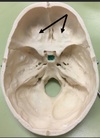

1. Identify the spaces labelled.

Anterior Cranial Fossa, Middle Cranial Fossa, Posterior Cranial Fossa

1. Identify the elevation. 2. What is the function of this structure?

1. Frontal Crest and Crista Galli 2. Attachment of Falx Cerebri, olfactory bulbs run lateral to it.

105

1. Foramen caecum 2. it transmits the emissary vein from the nose to the superior sagittal sinus. This has clinical importance in that infections of the nose and nearby areas can be transmitted to the meninges and brain from what is known as the danger triangle of the face.

106

1. Identify the elevation. 2. What is the function of this structure? 3. What structures are immediately lateral to this elevation? 4. This structure is perforated by what structures?

1. Crista Galli 2. Attachment of falx cerebri 3. Olfactory bulbs 4. Olfactory nerve rootlets

107

1. Identify the depression. 2. What structure is traversed through this depression if it is patent? 3. The structure identified in 2. connects which two areas? 4. When this structure is clinical significance if this structure is patent?

1. Foramen caecum 2. Emissary veins 3. Nose to superior saggital sinus 4. Infection can spread; meningitis

108

1. Identify the structures.

ORBITAL PLATES of Anterior Cranial Fossa

109

1. Identify the structure.

Dorsum of sellae pituitary gland rests here. Macroadenoma of pituitary will be seen as deviation of this in X-Ray

110

1. Identify the structure. 2. Name the structures passing through it

1. Optic canal 2. Optic nerve and opthalmic artery

111

112

1. Identify the structure. 2. What structure islodged here?

Hypophysial Fossa Pituitary Gland

113

1. Identify the structure. 2. What structure is lodged here?

1. Internal occipital crest 2. Falx cerebri attachment

114

1. Identify the structure. 2. What structures traverse this canal

1. Foramen Rotundum 2. Maxilliary nerve, V2 off trigeminal M.R Triangle R.O.S.L

115

1. Identify the structure. 2. What structure traverses this canal?

1. Superior Orbital Fissure 2. CN3,4,5 V1 off trigeminal, opthalmic artery

116

1. Foramen Spinosum 2. Middle Meningeal Artery, Meningeal branch of Mandibular Nerve Foramen Ovale (red arrow) Accessory Meningeal Artery, v3 c5 Mandibular Nerve, Lesser Superficial Vitrosal nerve, Emissiary nerve

117

1. Foramen Lacerum 2. The artery of pterygoid canal, the nerve of pterygoid canal. Internal carotid runs superiorly not through.

118

1. Identify the structure. 2. What produces this structure?

1. Petrous Crest 2. Sphenoid and occipital bones Arcuate Eminence due to Superior Semicircular Canal.

119

1. Identify the structure. 2. What structures traverse this canal?

1. Internal Acoustic Meatus 2. transmits the vestibulocochlear nerve, the facial nerve, and the labyrinthine artery (an internal auditory branch of the basilar artery). It also contains the vestibular ganglion. CN 7 & 8

120

1. Identify the structure. 2. What are the subdivisions of this structure? 3. What structures traverse these subdivisions?

1. Jugular Foramen, CN 9,10, 11 2. Anterior Intermediate, posterior 3. The anterior compartment transmits the inferior petrosal sinus and glossopharyngeal nerve (CN IX) The intermediate transmits the vagus and accessory nerves (aka cranial nerves number X, and XI respectively). The posterior transmits the sigmoid sinus (becoming the internal jugular vein) and some meningeal branches from the occipital and ascending pharyngeal arteries.

121

1. Identify the canal. 2. What structures traverse this canal?

1. Hypoglossal canal 2. Hypoglossal Nerve

122

1. Formaen Magnum 2. Spinal cord, CN11 accessory, vertebral arteries.